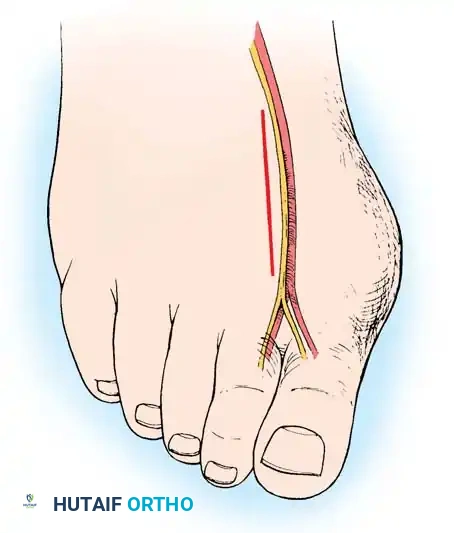

• Begin the second stage with a dorsal longitudinal incision beginning 2 to 3 mm proximal to the dorsal aspect of the fi rst web space to avoid web contracture postoperatively; extend it proximally between the fi rst and second metatarsal heads for 3 to 4 cm (Fig. 78-18). This allows adequate exposure of the adductor insertion into the base of the proximal phalanx, the lateral head of the fl exor hallucis brevis muscle converging on the fi bular sesamoid, and the entire lateral capsule from the extensor hallucis longus muscle to the plantar plate.

• Delicate retraction of the skin exposes the dorsal digital branches of the veins, which should be cauterized if they obscure the deeper dissection. The terminal branches of the fi rst dorsal intermetatarsal artery may be encountered at a location adjacent